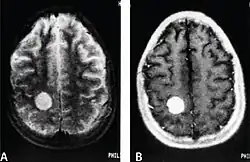

| MRI of a cardiac angiosarcoma that has metastasised to the brain. | |

Primary cardiac angiosarcoma

Primary cardiac angiosarcoma is an angiosarcoma that arises in the heart. Despite being very rare they are the most common malignant primary heart tumor with 10–25%[12][3] of cases being angiosarcomas. Symptoms may include shortness of breath, chest pain (46%[12]), hypotension and syncope. Superior vena cava syndrome is reportedly a complication of cardiac angiosarcoma.[7] Due to the non-specificity of symptoms and rarity of the disease it is often missed by doctors and initial diagnosis may be delayed. A 2012 study reported that 56% of patients presented with pericardial effusion with or without cardiac tamponade.[12] The most common finding on imaging is cardiomegaly. Prognosis is generally very poor with a mean survival rate of three months to four years following diagnosis.[7] Metastasis at time of diagnosis is common.[12]